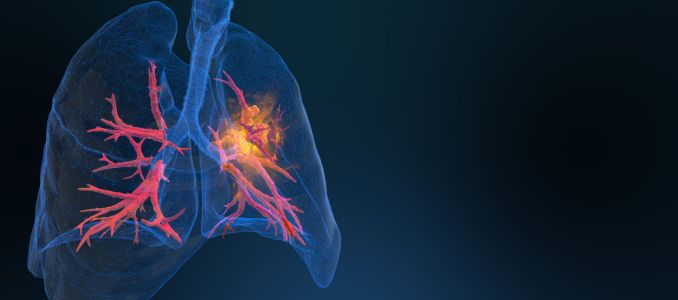

NIOSH is offering free screenings to help coal miners identify black lung disease early and track respiratory health impacts from coal mine dust exposure.